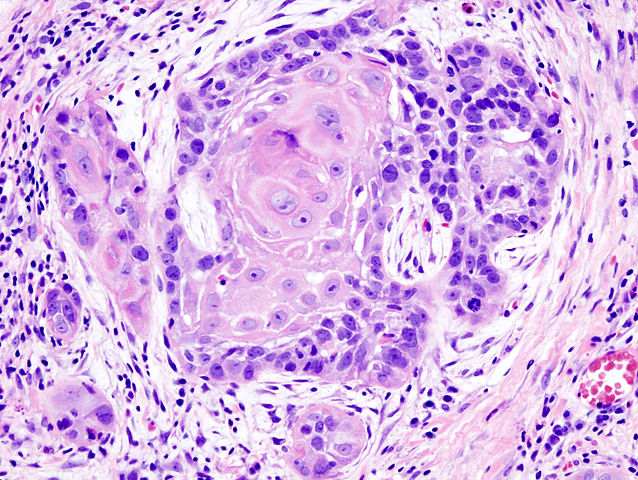

Squamous cell carcinomas are a cancer of the skin (and other parts of the body) that are characterized by malignant tumors that develop in epithelial keratinocytes, or the cells that produce keratin. It is the second most common skin cancer within the white population, with basal cell carcinoma being the first most common skin cancer. Squamous cell carcinoma incidence has grown by 50 to 200% over the past 10 to 30 years, based on various studies. Squamous cell carcinomas are also geographically-dependent in populations of which it affects: for instance, there is a 50-fold increase in rates when comparing Northern Europe to Australia.

Squamous cell carcinoma-diagnosed patients usually have tumors on sun-exposed areas that are often in the form of firm nodules, which can be small. Squamous cell carcinomas lack translucence, unlike basal cell carcinoma tumors.

- Occurring in the squamous (surface) keratinocytes of the epidermis

- Invasive tumors result in firm papules or plaques that are pink or skin-colored

- More likely than basal cell carcinomas to metastasize, but still rare